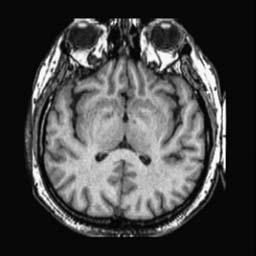

To demonstrate the effectiveness and efficiency of the proposed image fusion method , we conduct a set of comparative experiments on three image datasets. The first is composed by 8 pairs of multi-modal medical images and the second one contains 15 pairs of multi-focus gray or color natural images. These two datasets are often used in many related papers and some examples are shown in Figure 3(a) and Figure 3(b). The third one is a new multi-focus cervical cell image dataset collected by ourselves, which consists of 15 groups of color images and each group contains a series of multi-focus cervix cell images with size of or , etc. Some source examples are shown in Figure 3(c). Our source code implemented in C++ along with the new multi-focus cervical cell image dataset is available online.

We first evaluate the performance of the proposed method under varying total number of octaves and number of layers sampled per octave. The fused images of a pair of multi-modal medical images with different and are shown in Figure 4. In this example, on the one hand, when only 1 or 2 octaves are involved in constructing the DoG pyramid, the fused images fail to keep the integrity information of large size objects (e.g. eyeballs), while by increasing the value of , the integrity information of eyeballs is preserved. On the other hand, although not as significant as the increase of octave numbers , the fused image can contain more details by the increase of layer numbers . The corresponding objective quality metrics are shown in Figure 5. As shown in Figure 5(a), most of the metric values are improved as the number of octaves increases with the fixed layer numbers 3 in the global tendency and each of them tends to be stable when the number of octaves is 5. To get a relatively good quality from Figure 5(b), we can notice that some of the metric values can get a good performance when the number of layers is 3, such as the MI, SSIM, QI and VIF, though there are only a little change of all the metric values by increasing the number of layers with the fixed octave numbers 5. Because it will result in more computation burden with the increase of the value and , and for different kinds of source images, there are different performance with the diverse parameter settings. To get a trade-off between them in our experiments, we set for the multi-modal dataset, for the natural datasets and for the multi-focus cell dataset, respectively.

Figure 6 shows the fused images obtained by different methods with the multi-modal source images shown in Figure 3(a). As shown in these figures, the proposed method can produce images which preserve the complementary information of different source images well. Moreover, due to the scale-invariant structure saliency selection, our method can keep the integrity information of large size objects and the visual details simultaneously. Although the fused image generated by other methods can also capture the details to some extent, all of them fail to keep the integrity information of large size objects such as the eyeballs. Furthermore, from Figure 6(k)-6(t), the DTCWT, GFF, IM and NSCT methods may decrease the brightness and contrast while the proposed method can preserve these features and details without producing visible artifacts and brightness distortions.